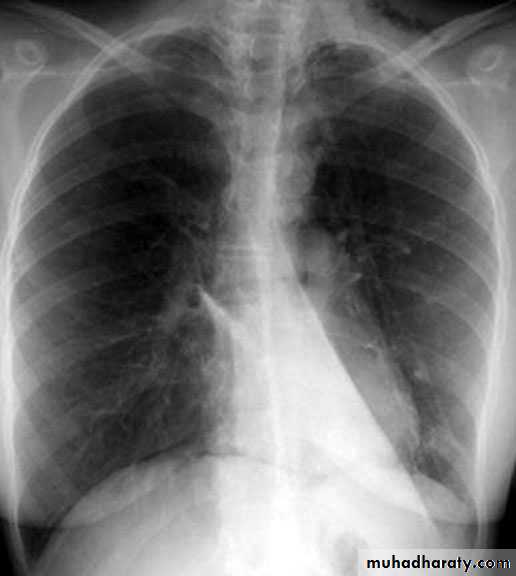

The pleura :

• Pleural effusion : collection of fluid within the pleural space. This can be further divided into Transudate , exudate, according to protein content .Other type of fluid collection within pleural space are

empyema (pyothorax)

chylothorax (lymph in pleural space )

haemothorax

• Chest x-rays are the most commonly used examination to assess for presence of a pleural effusion, however it should be noted that on a routine erect frontal chest x-ray as much as 200-500 ml of fluid is

• required before it becomes evident .

blunting of the costophrenic angle

blunting of the cardiophrenic angle

fluid within the horizontal or oblique fissures

eventually a meniscus will be seen, on frontal films seen laterally and gently sloping medially

with large volume effusions, mediastinal shift occurs away from the effusion

• Lateral films are able to identify a smaller amount of fluid ( about75%)as the costophrenic angles are deepest posteriorly posteriorly

Pleura effusion signs

Obliteration of costo-pherinic anglesMeniscus sign

Lenticular sign